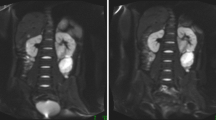

Example ADC maps and mono-exponential curve fits for ADC0-1000 and ADC100-1000 from intracranial and extracranial tumour patients are shown in Figs. 2 and 3, respectively. The IAUGC60 and Ktrans maps and contrast agent uptake curves (same patients) are shown in Figs. 4 and 5.

(a) ADC100-1000 map from a 10-year-old boy with glioblastoma multiforme in the left frontal lobe. (b) Example mono-exponential curve fits using signal intensities at b = 0 – 1000 sec/mm2 (blue) and b = 100 – 1000 sec/mm2 (red) from a single pixel in the tumour. The calculated ADC value for the two fits were 1402 × 10-6 mm2/sec and 1228 × 10-6 mm2/sec, respectively

(a) ADC100-1000 map from a 13-year-old boy with a low grade spindle cell sarcoma attached to the right chest wall. The signal void seen in the top left region is due to a saturation band placed over the heart to avoid propagation of artefacts due to cardiac motion. (b) Example mono-exponential curve fits using signal intensities at b = 0 – 1000 sec/mm2 (blue) and b = 100 – 1000 sec/mm2 (red) from a single pixel in the tumour. The calculated ADC value for the two fits were 1626 × 10-6 mm2/sec and 1221 × 10-6 mm2/sec, respectively